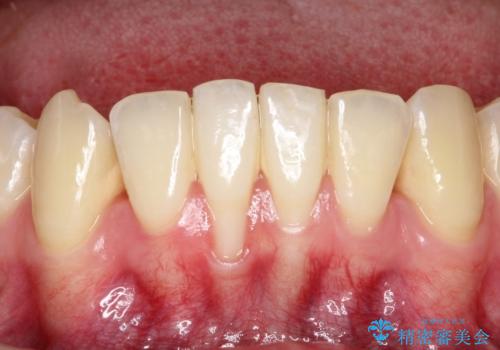

下顎前歯の歯肉退縮 結合組織を用いた根面被覆

- 歯肉退縮を主訴に来院された患者様です。

口蓋から結合組織を採取して、根面被覆を行いました。

十分な根面被覆を達成で患者様にも満足していただけました。